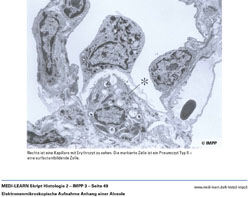

• Elektronenmikroskopische Aufnahme Anhang einer Alveole

• Histologie der Alveolen und Blut-Luft-Schranke